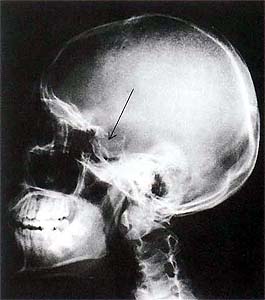

(1)頭部のレントゲン撮影

腫瘍の大きさがおよそ1cm以上になってくると、脳下垂体のハレが通常のレントゲン撮影でもわかってきます(下図の矢印)。しかし、これだけでは確実な診断は出来ません。